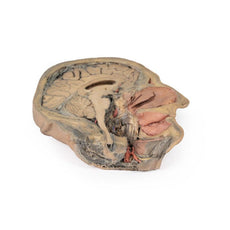

The head and neck of the specimen provides views of both superficial and deep structures in the region. The calotte has been removed ~2cm superior to the orbits to expose the brain in relation to the endocranial cavity. The transverse section through the cerebrum demonstrates the relation of the grey matter cortex to the white matter medulla, as well as the lateral ventricles with a small amount of choroid plexus visible in the base of both spaces. The skin and superficial fascia on the right side has been retained and false-coloured to display the angiosomes of the face and posterior neck. On the left side, the superficial tissues have been dissected to expose the muscles of facial expression, muscles of mastication, and deeper structures of the infratemporal fossa including the lingual nerve, terminal branches of the external carotid artery into the superficial temporal and maxillary arteries.

The head and neck of the specimen provides views of both superficial and deep structures in the region. The calotte has been removed ~2cm superior to the orbits to expose the brain in relation to the endocranial cavity. The transverse section through the cerebrum demonstrates the relation of the grey matter cortex to the white matter medulla, as well as the lateral ventricles with a small amount of choroid plexus visible in the base of both spaces. The skin and superficial fascia on the right side has been retained and false-coloured to display the angiosomes of the face and posterior neck. On the left side, the superficial tissues have been dissected to expose the muscles of facial expression, muscles of mastication, and deeper structures of the infratemporal fossa including the lingual nerve, terminal branches of the external carotid artery into the superficial temporal and maxillary arteries.